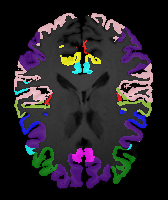

Moving Target Mono-0 Mono-5 DA-1 DA-5 Mono-200 Refer to caption Refer to caption Refer to caption Refer to caption Refer to caption Refer to caption Refer to caption Refer to caption Refer to caption Refer to caption Refer to caption Refer to caption Refer to caption Refer to caption

Image Manual Seg DA-1 Mono-21 DA-21 Mono-65 Refer to caption Refer to caption Refer to caption Refer to caption Refer to caption Refer to caption

Figure 2:  Examples of knee MRI registration (top) and brain MRI segmentation (bottom) results. Top: The first two columns are the moving image/segmentation and the target image/segmentation followed by the warped moving images (with deformation grids)/segmentations by different models. Bottom left to right: original image, manual segmentation, and predictions of various models. Mono-i𝑖i and DA-i𝑖i represent the mono- and DA models with i𝑖i manual segmentations respectively.

Results: All trained networks are evaluated using Dice overlap scores between predictions and the manual segmentations for the segmentation network, or between the warped moving segmentations and the target segmentations for the registration network. Tabs. 1 and 2 show results for the knee and brain MRI experiments respectively in Dice scores (%). Fig. 2 shows examples of knee MRI registrations and brain MRI segmentations.

Qualitative results: DA achieves more anatomically consistent registrations than the mono-networks on the knee (Fig. 2) and Brain MRI samples (see supplementary material).

Moving Target Mono-0 Mono-21 DA-1 DA-21 Mono-65 Refer to caption Refer to caption Refer to caption Refer to caption Refer to caption Refer to caption Refer to caption Refer to caption Refer to caption Refer to caption Refer to caption Refer to caption Refer to caption Refer to caption

Image Manual Seg DA-1 Mono-5 DA-5 Mono-200 Refer to caption Refer to caption Refer to caption Refer to caption Refer to caption Refer to caption

Figure 4: Examples of brain MRI registration (top) and knee MRI segmentation (bottom) results. Top: The first two columns are the moving image/segmentation and the target image/segmentation followed by the warped moving images/segmentations by different models. Bottom left to right: original image, manual segmentation, and predictions of various models. Mono-i𝑖i and DA-i𝑖i represent the mono- and DA models trained with i𝑖i manual segmentations respectively.